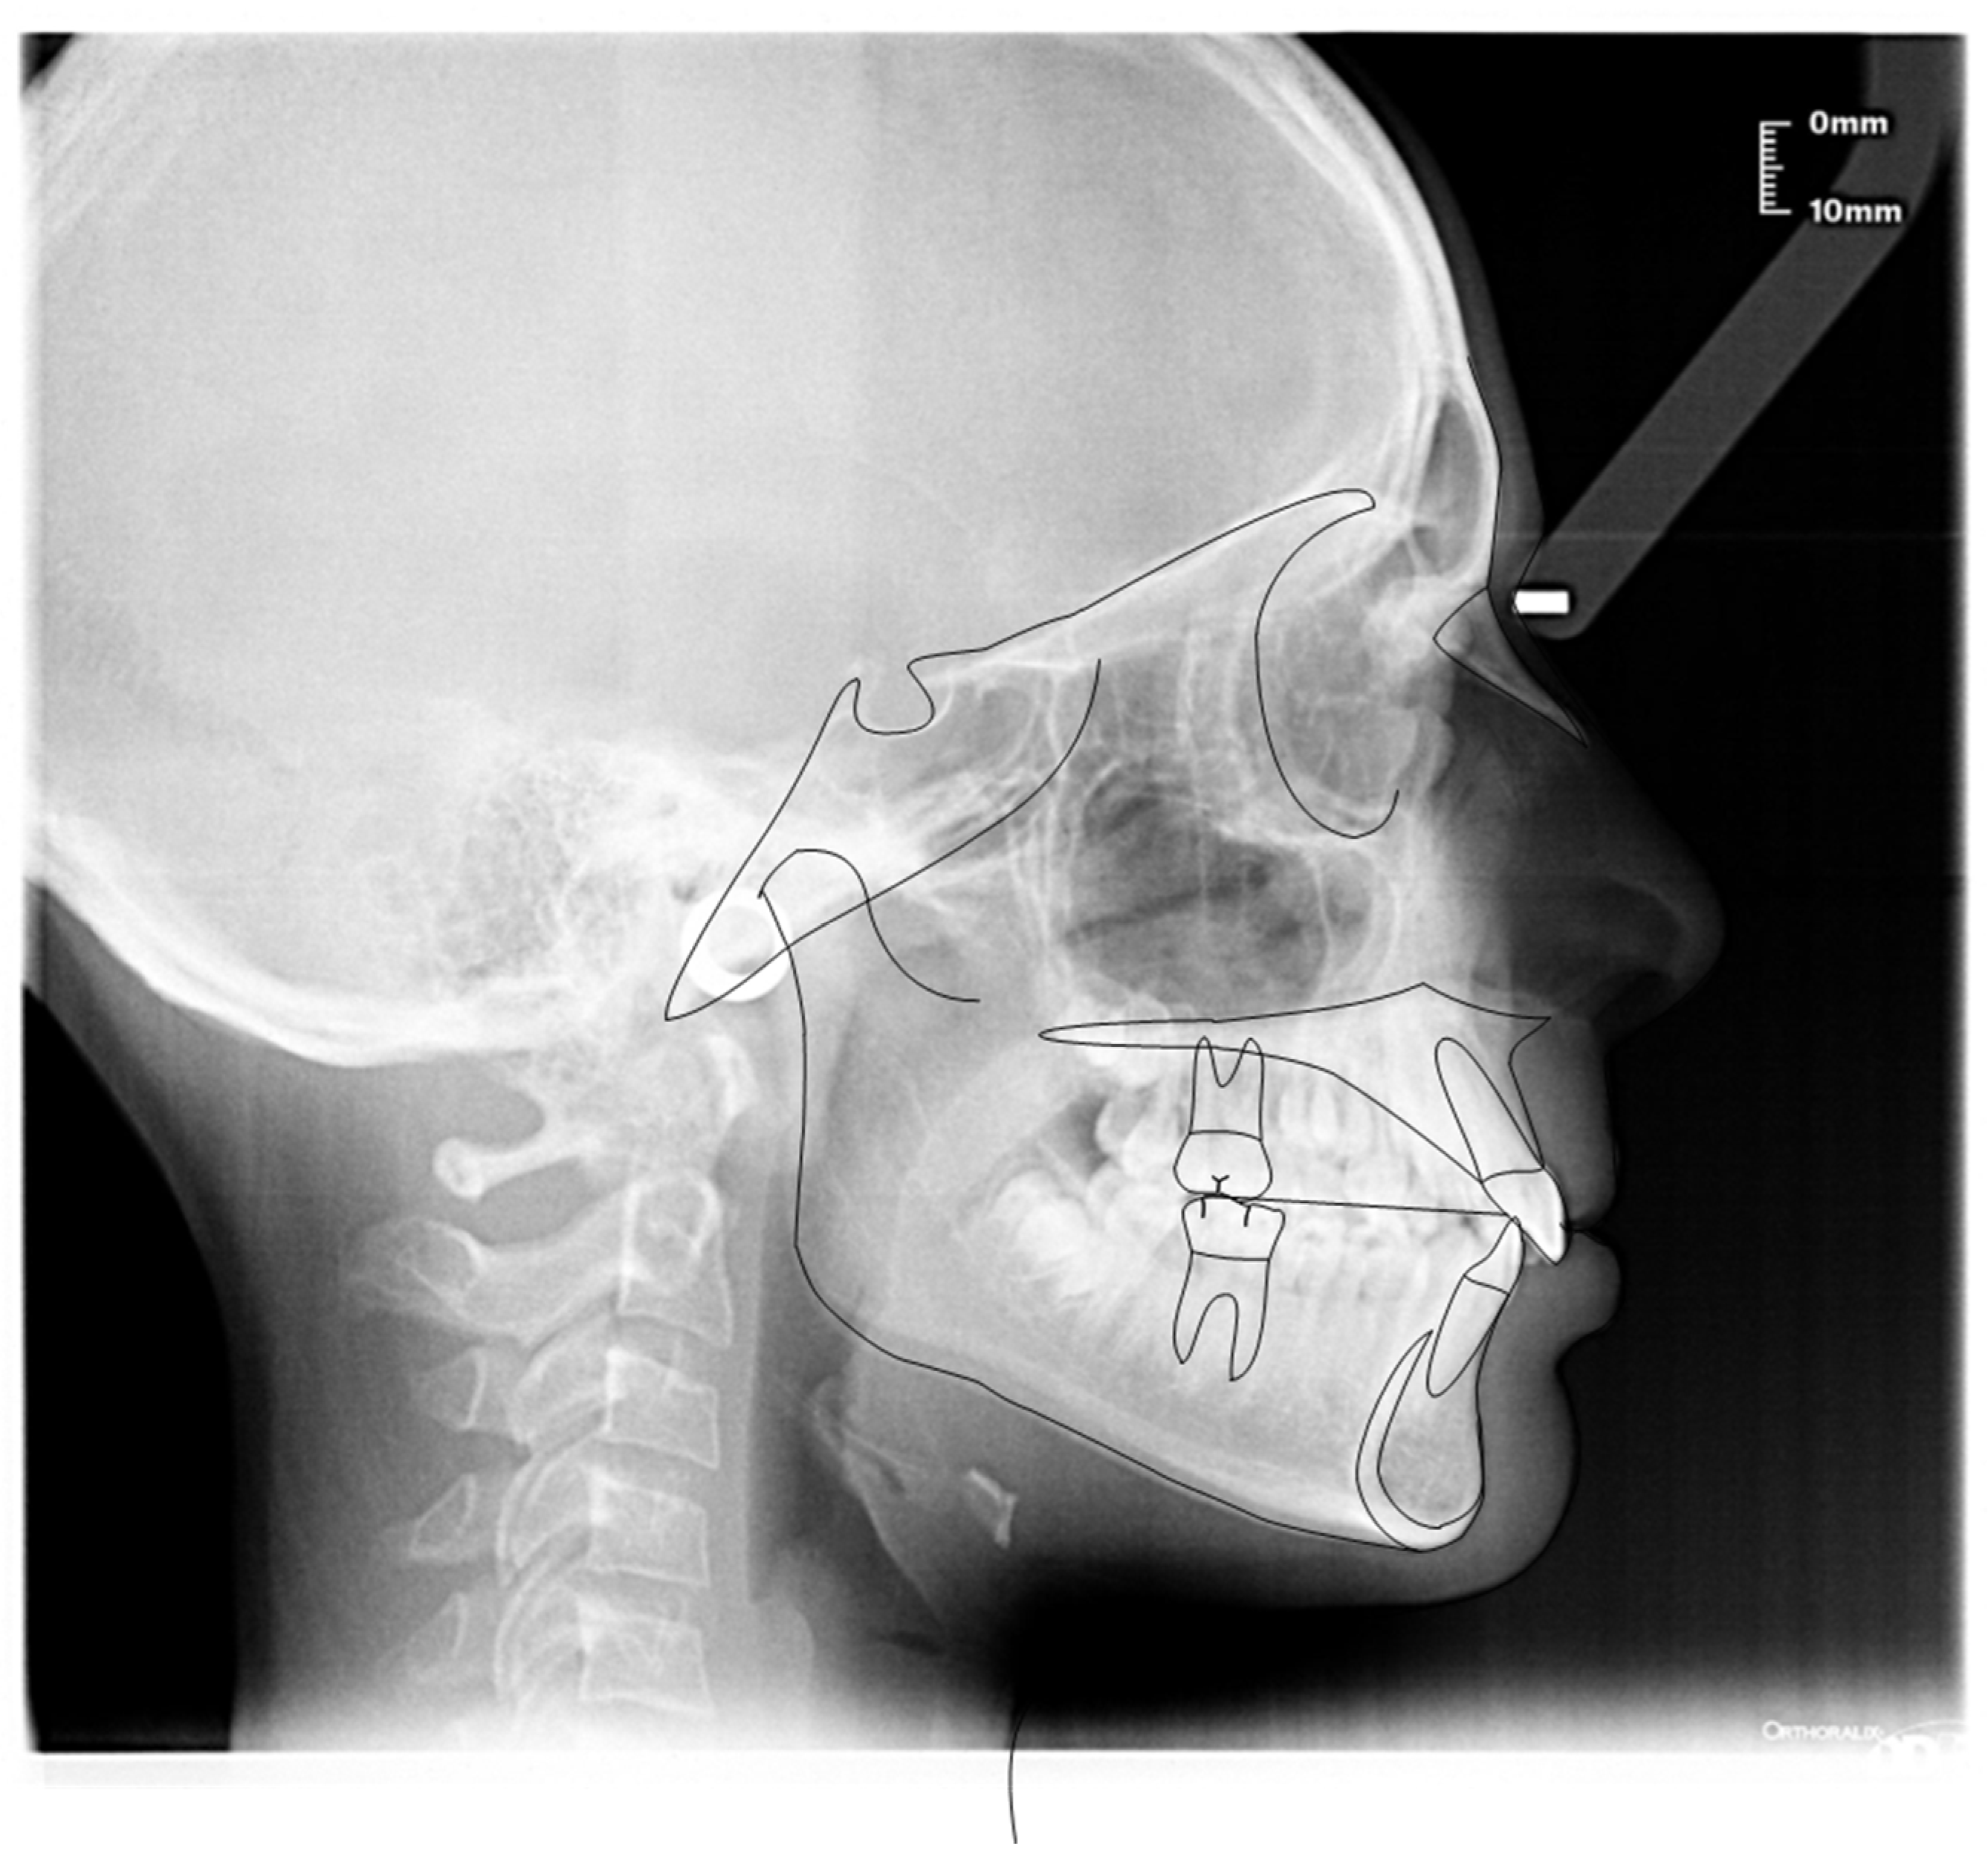

3.1. Clinical Case #1

3.2. Clinical Case #2

3.3. Clinical Case #3

3.4. Clinical Case #4